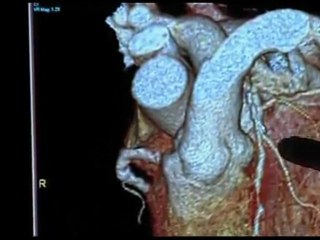

Angiography